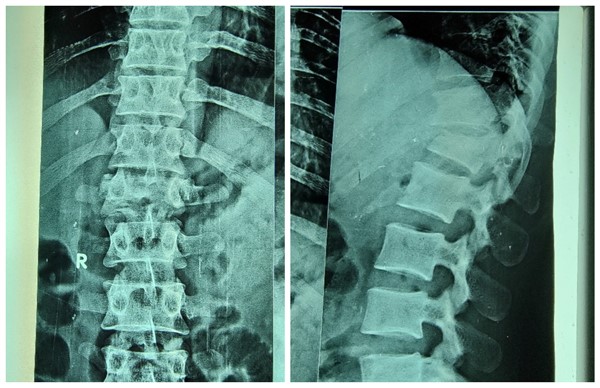

周二一大早,苏丹恩图曼友谊医院骨科门诊就传来了家属急切的声音:“撒艾德 艾黑”,“帮帮我的兄弟”(中文意)。原来是,31岁的法拉赫,一月前不慎从高处坠落,当即出现腰痛,双下肢活动受限,大小便失禁。拍片显示腰1压缩骨折。来自援苏丹医疗队骨科的高宗强副主任医师阅片后和家属详细沟通病情,考虑“腰1压缩骨折伴脊髓受压”,当时就建议手术治疗。因患者家庭经济较紧张,家里一下就丧失了主要劳动力,患者又行动困难,患者及家属多方商议并考虑再三,再次在骨科门诊当面咨询,高宗强副主任医师耐心细致的解答了患者及家属的顾虑,详细讲解了准备实施的手术方案,及可能出现的风险及意外,并与身为骨科大夫的医院院长阿明商议,最大可能的控制手术的费用。病人家属信任的眼神,对手术后康复的急切渴望,这一切都对援苏丹中国医生的肯定。患者入院时,已经是受伤后1月了。入院查体:胸腰段有明显叩击痛,左下肢肌力2级,右下肢肌力3级,双侧足背感觉减退,尿管导尿。

脊髓损伤,在医学领域是世界性难题。一旦损伤,恢复难度很大。所以临床上,一旦出现脊柱骨折造成压迫出现脊髓损伤症状,原则上尽早手术,尽早解除压迫,才有可能更好的帮助神经恢复。但苏丹处于非洲北部,是联合国认定的世界最不发达国家之一,医疗条件相对不足,当地人民经济条件较差。一般病人骨折后,得知需要手术治疗,经过反复考虑,多方筹措住院手术费用,而这,往往已经是几个月后的事情了。这个患者在受伤后一个月住院手术,原则上确实错过了最佳手术时机。但在苏丹当地来说,已经算是治疗相对比较及时了。患者毕竟才31岁,还是家里的顶梁柱,人生的路还很长,还寄托着很多人的希望。做手术还能给脊髓损伤的恢复创造一个良好的条件,如果不做手术,恢复希望渺茫,也许他一辈子就只能与轮椅相伴了。